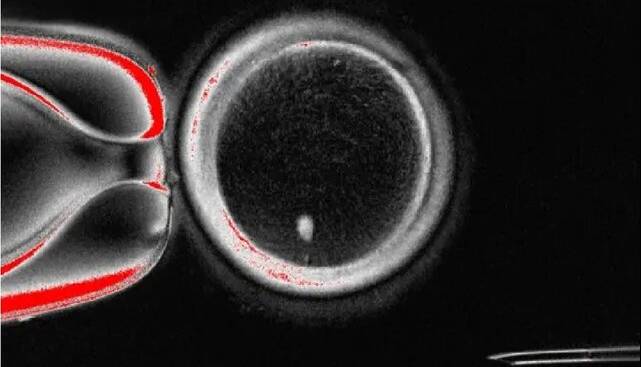

نتیجه، یک تخمک هاپلوئید بود که می‌توانست از طریق لقاح مصنوعی(IVF) استاندارد با اسپرم لقاح داده شود و جنین‌هایی با ورودی ژنتیکی برابر از هر دو والدین تشکیل دهد.

محققان در این مطالعه، 82 تخمک عملکردی تولید کردند و آنها را با اسپرم لقاح دادند. در حالی که اکثر آنها در مرحله 4 تا 8 سلولی به دلیل ناهنجاری‌های کروموزومی متوقف شدند، حدود 9 درصد روز پس از لقاح به مرحله بلاستوسیست رسیدند.